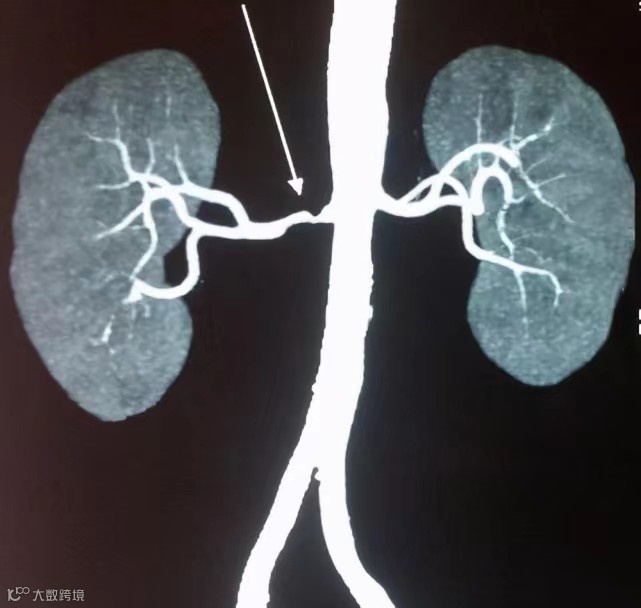

2023年3月14日,是第19个世界肾脏日,主题为“人人享有肾脏健康——促进医疗平等,优化用药实践”为主题”。肾脏在人体中的重要性不言而喻,被称为"第二心脏",具有调节血压、维持电解质和代谢等功能。人体为肾脏输血的血管被称为肾动脉,其通畅程度直接影响肾脏健康,不容忽视。一些发生在中青年人群中不明原因的高血压,往往是肾动脉狭窄所致。

高血压分为原发性高血压和继发性高血压,而肾血管性高血压属于继发性高血压的一种,是由于肾动脉狭窄导致的,肾动脉狭窄造成肾脏缺血,肾脏分泌一种叫“肾素”的物质,“肾素”会引起血管使劲收缩,从而导致血压升高。

其实肾动脉狭窄是一种可治愈的疾病,手术缓解了狭窄后,肾脏血流动力学改善,不仅能纠正高血压,而且能保护受损的肾功能。因此,早期诊断与治疗就显得尤为重要。